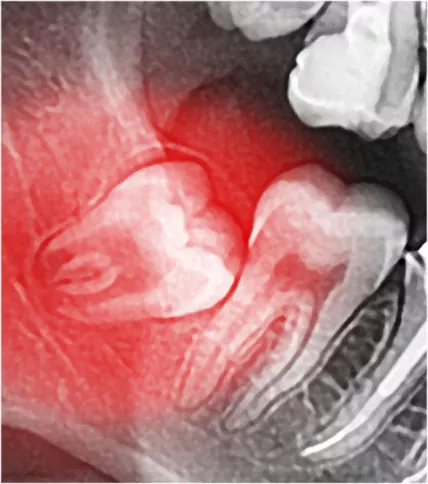

X-Ray of wisdom teeth.

Wisdom Teeth Removal

We provide wisdom teeth assessment for removal and perform extractions if needed. Learn more about your wisdom teeth and why they may need to be extracted.